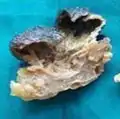

Gross pathology of a cystic nodular hidradenoma

Gross pathology of a cystic nodular hidradenoma Dermal duct tumor